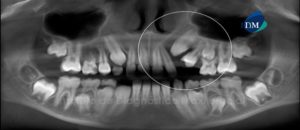

Paciente masculino de 16 años de edad es referido al Instituto de Diagnóstico Maxilofacial (IDM) para su evaluación y diagnóstico. A la evaluación de la